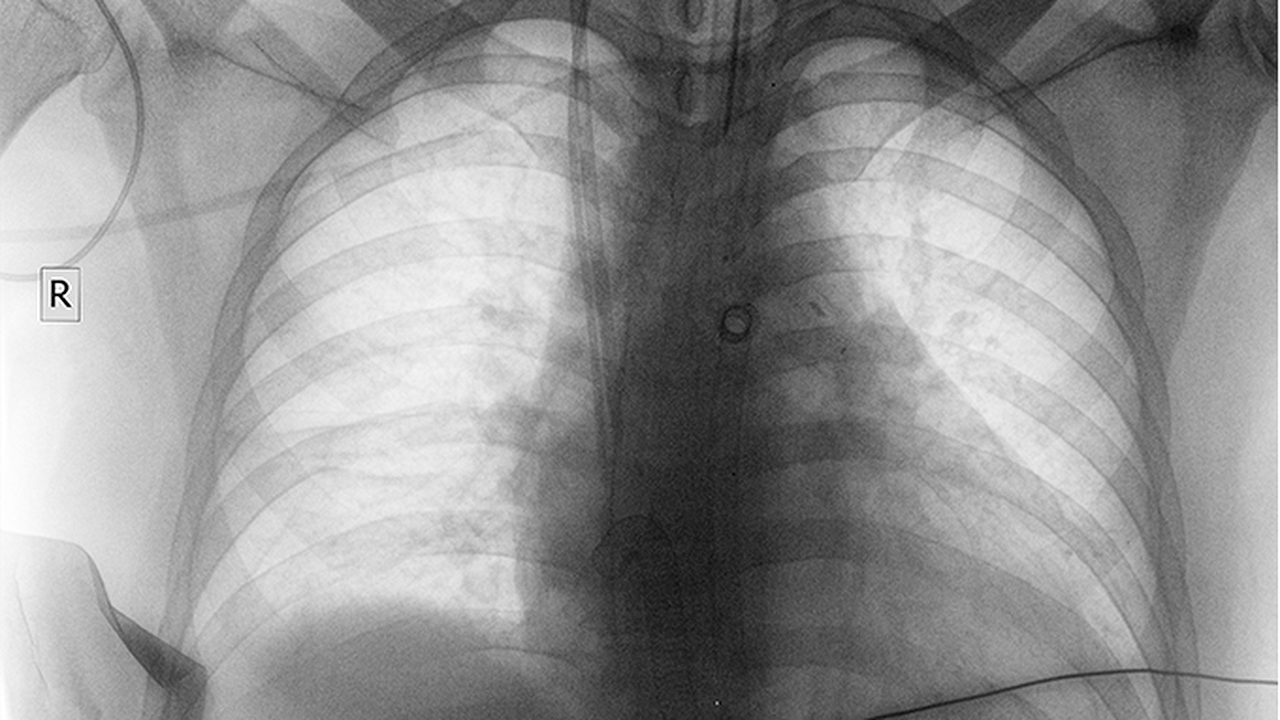

肺癌的发病原因复杂,长期吸烟、空气污染、职业暴露(如石棉、砷等)及遗传因素均为高危诱因。早期筛查和规范化治疗对提高生存率至关重要。